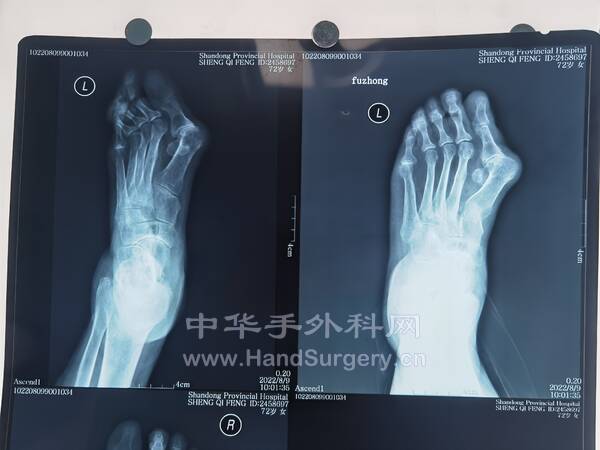

今日得偿所愿,上午跟着老师参观双侧青少年柔韧性扁平足微创扁平足制动器矫正术,双侧副舟骨切除胫后肌腱止点重建术的

13岁男性患者,用的威高扁平足制动器(但大博2代扁平足制动器相对较好)。

副舟骨切除,用直径3.0mm可吸收螺钉固定,与胫后肌腱加固缝合,腱骨缝合,用2.5mm克氏针在舟骨上打孔,放入强生直径3.0mm可吸收铆钉(丝线亦为50%可吸收线),远端与胫后肌腱编织缝合加固!术后6周不能行走。